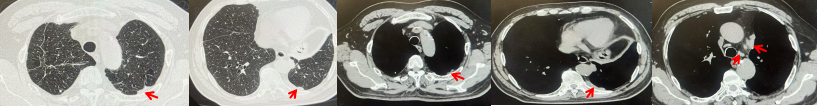

2024.11.19患者出现右侧胸痛,复查胸部CT检查示右侧胸膜肿物,大小约31mmX24mm,右侧4、5肋骨骨质破坏,考虑转移(如图2)。建议患者穿刺活检取病理明确诊断,患者拒绝,经MDT会诊后结合影像学表现及病史考虑为胸膜转移,肋骨转移,分期为rT0N0M1a IVA期,DFS仅仅17个月。2024.12.05起行信迪利单抗联合培美曲塞+卡铂方案治疗4周期,复查胸CT评效PR(如图3)。之后给予信迪利单抗+培美曲塞维持治疗6周期,期间复查CT评效PR(如图3)。目前信迪利单抗+培美曲塞维持治疗中,截止至目前PFS约为8个月,治疗期间未出现明显毒副反应。

图2:患者胸膜及肋骨转移(2024.11)胸部CT肺窗、纵隔窗及骨窗

71岁男性,高血压病史20年,口服药物治疗,无糖尿病、心脏病等基础疾病,吸烟史50年,20支/天,已戒1年余,无饮酒史,无肿瘤家族史。2023.11因咳嗽、咳痰行胸CT检查:左肺下叶占位性病变,大小约12mmx8mm(如图5)。2023.11.20行“单孔胸腔镜左肺中下叶切除、肺门及纵隔淋巴结清扫、胸膜粘连松解术”;术后病理:(左肺下叶)结合免疫组化鳞状细胞癌(中、低分化),局部见脉管内癌栓,未见确切神经侵犯,(气管切缘)净。(淋巴结)未见转移癌0/19(4组0/1;5组0/1;6组0/2;7组0/1;9组0/1;10组0/2;11组0/3;12组0/2;13组0/2;14组0/4)。术后分期pT1bN0M0 IA期,术后定期复查。

2024.09.12复查胸部CT示左侧胸膜结节,大者约为27mmx13mm,考虑转移可能性大,纵隔淋巴结增大,恶性?(如图6)。患者行胸膜穿刺活检取病理,结果示(胸膜)结合免疫组化,支持鳞状细胞癌,PD-L1(克隆号28-8)TPS约20%。分期为rT0N2bM1a IVA期,DFS为10个月。2024.09.24起行替雷利珠单抗联合紫杉醇+卡铂方案治疗4周期,复查胸CT评效SD(如图7)。后患者因脑梗塞停止治疗,于综合医院就诊,后未返院复查及治疗。

图5:患者手术前(2023.11)胸部CT肺窗及纵隔窗

图6:患者胸膜及纵隔转移(2024.09)胸部CT肺窗及纵隔窗